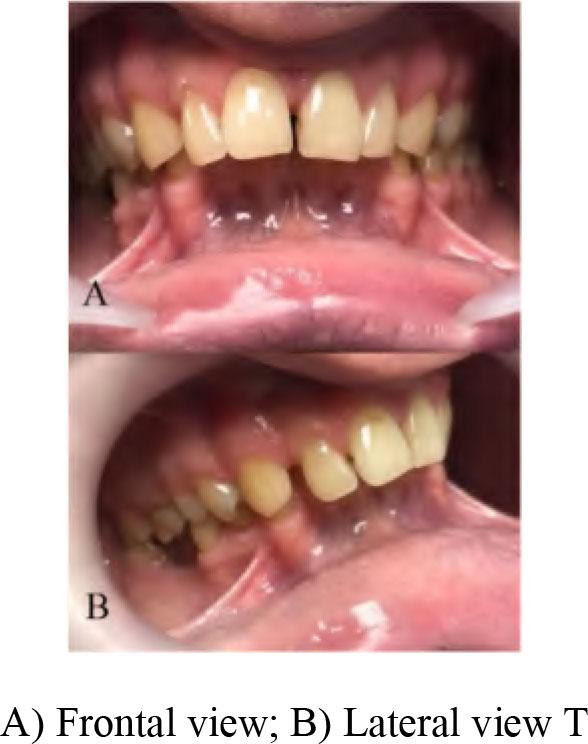

A 45-year-old male patient was referred to the Department of Prosthodontics, Faculty of Medical Sciences, University of Kragujevac with a chief complaint of protruded maxillary anterior teeth, teeth malalignment, unpleasant aesthetics and difficulty in chewing. The patient had no history of any medical problems. Extraoral examination revealed a convex profile with mild mandibular retrusion, an obtuse nasolabial angle and an everted lower lip. There was no masticatory and facial muscle hyperactivity and no signs of temporomandibular disfunction (TMD). On intraoral examination a severe deep-bite and an increased overjet with anterior maxillary protrusion were detected (Figure 1).

Initial oral examination.

The anteroposterior discrepancy of the anterior teeth was very severe and the mandibular incisal edges were occluded with the palatal tissues in the opposing arch. An overbite of 9 mm and an overjet of 12 mm were observed. There was clinical evaluation of reduced VDO. The patient’s interocclusal space that was measured between nose and chin tips was 8–9 mm (the difference between physiologic rest position of the mandible and VDO). Furthermore, facial analysis revealed that the maxillary midline was coincident with the facial midline but there was slight deviation of the mandibular midline to the right. Steiner cephalometric analysis was done. The angle of the ANB is greater than 4, by measuring it is 6. The angle of I/Spp is less than 70, by measuring it is determined to be 63. With this analysis, we determined that it is a skeletal irregularity of the II skeletal class with protrusion of the upper incisors. The patient was diagnosed as an Angle Class II division 1 malocclusion.